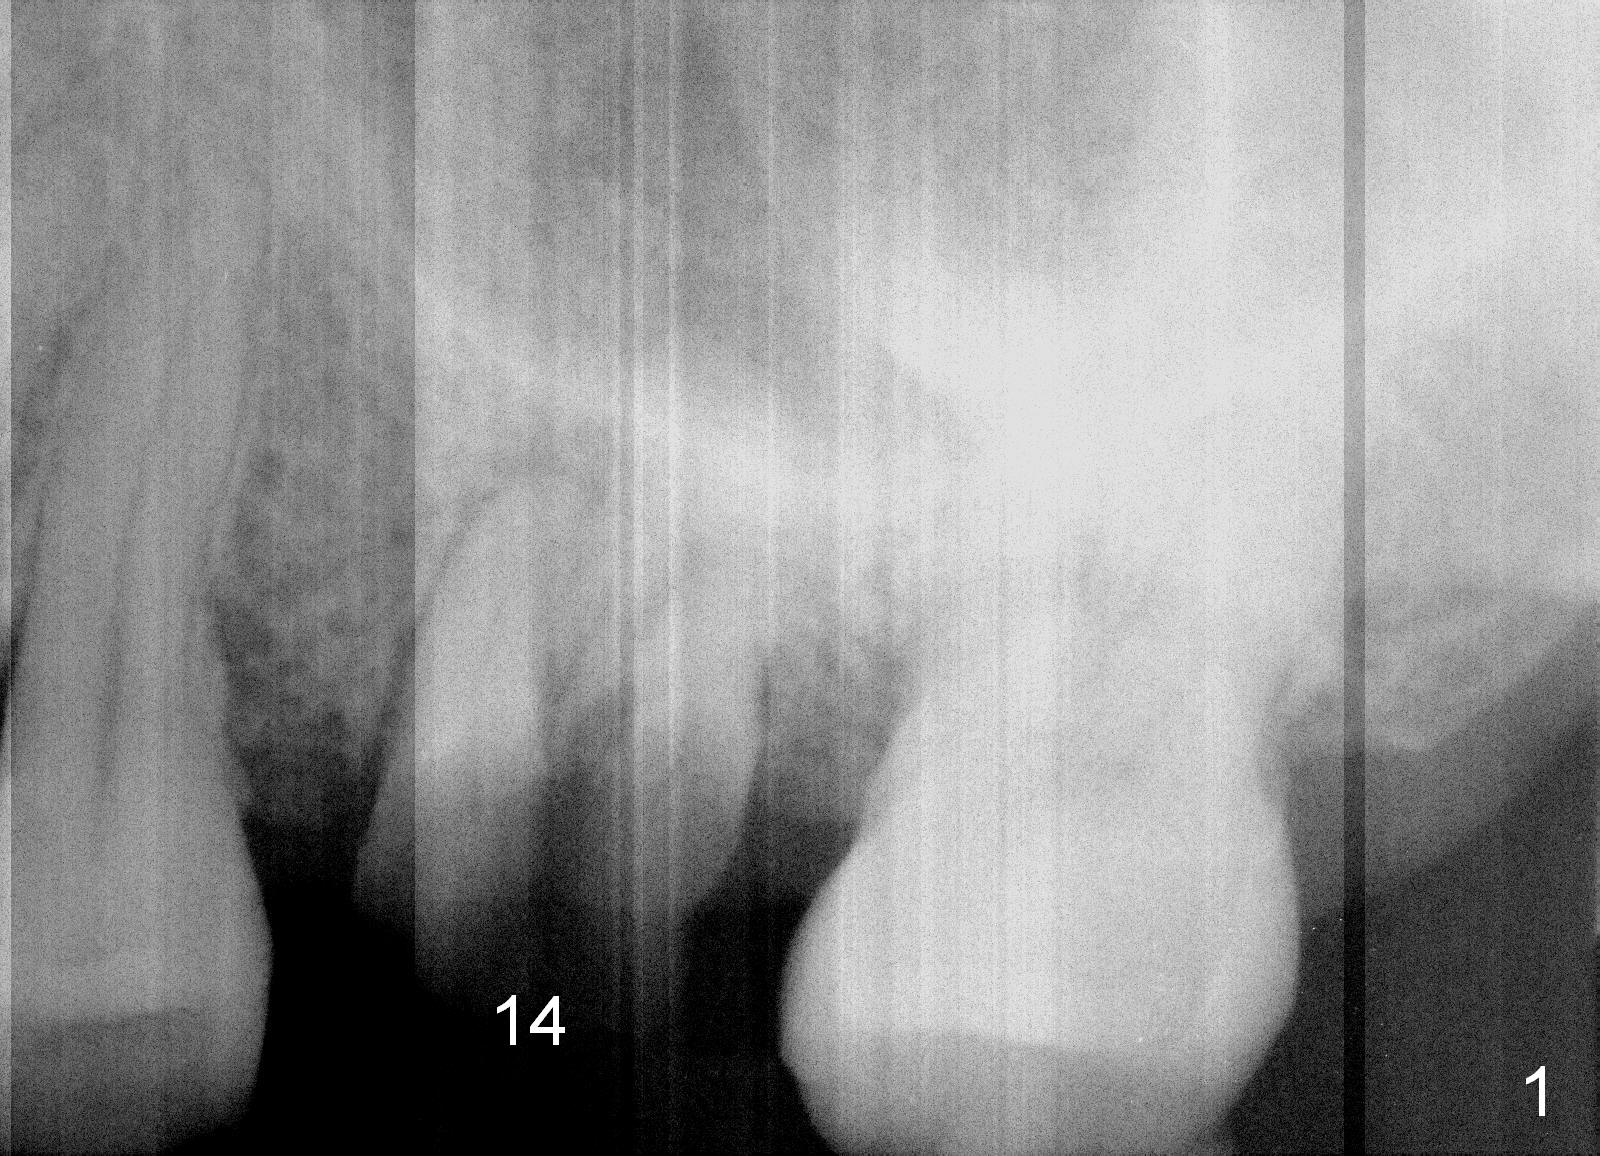

A 49-year-old man requests to restore #14 with residual roots (Fig.1). There is periapical radiolucency (Fig.2 *). A 5.9x10 mm bone-level implant is placed with minor sinus lift (Fig.3), whereas a short (Fig.4) or long (Fig.5) tissue-level implant is placed without or with sinus lift. The implant could be as large as 7 mm (Fig.5) to prevent post-extraction ridge atrophy.

It appears that the palatal root (Fig.6 P) is separated from the buccal ones (MB, DB). Connection between the latter appears to be weak (Fig.2) and could be broken using proximators or small straight elevator.